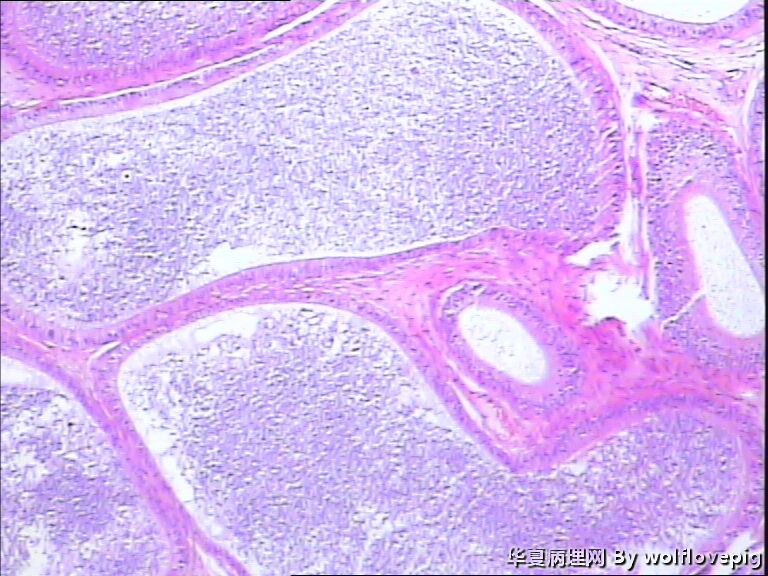

62y,双侧附睾。

临床怀疑结核,以附睾结节切的,取材时未发现明显结节。

送检附睾管囊性扩张,管腔结构较完整,多数管腔内见精子积聚,少数管腔内有出血。

取材切片附睾管扩张,精子淤积,部分区域出血

未见肉芽肿结构,也未见其它异常。